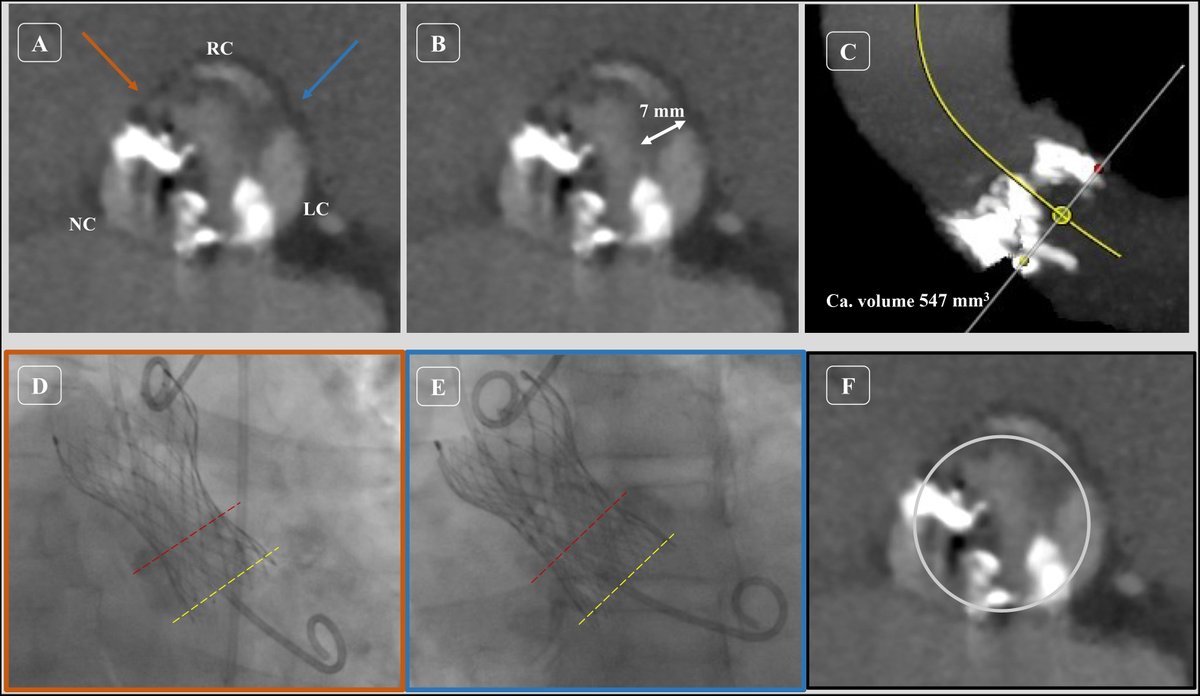

Fantastic case in Tactical course, guided by Avvigo II system essential in challenging scenarios with final stenting Synergy XD 48 mm brilliant deliverability . Great manage by @helenatmCARDIO Héctor Cubero Gallego Beatriz josep Rut Álvarez Velasco